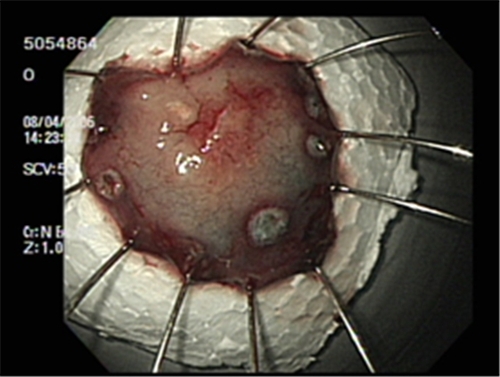

위산이 역류하게 된다면 속이 쓰리게 되고 있는데 위암의 초기증상일 수 있다고 합니다. 약을 복용해도 속쓰림이 이어진다면 암세포 증식의 가망이 있으니까 소화불량과 같이 증상이 발생한다면 내시경 검사를 받아보세요. 약을 섭취하도록 하면 치료가 간단하여 사소하게 여기고 지나쳐 버릴 수 있고요 약을 섭취했음에도 계속하여 속 쓰림 증상이 계속된다면 이는 암세포가 증식하고 있을 가능성이 높므로 정밀 검사를 받아보는 게 좋을듯 똑같습니다